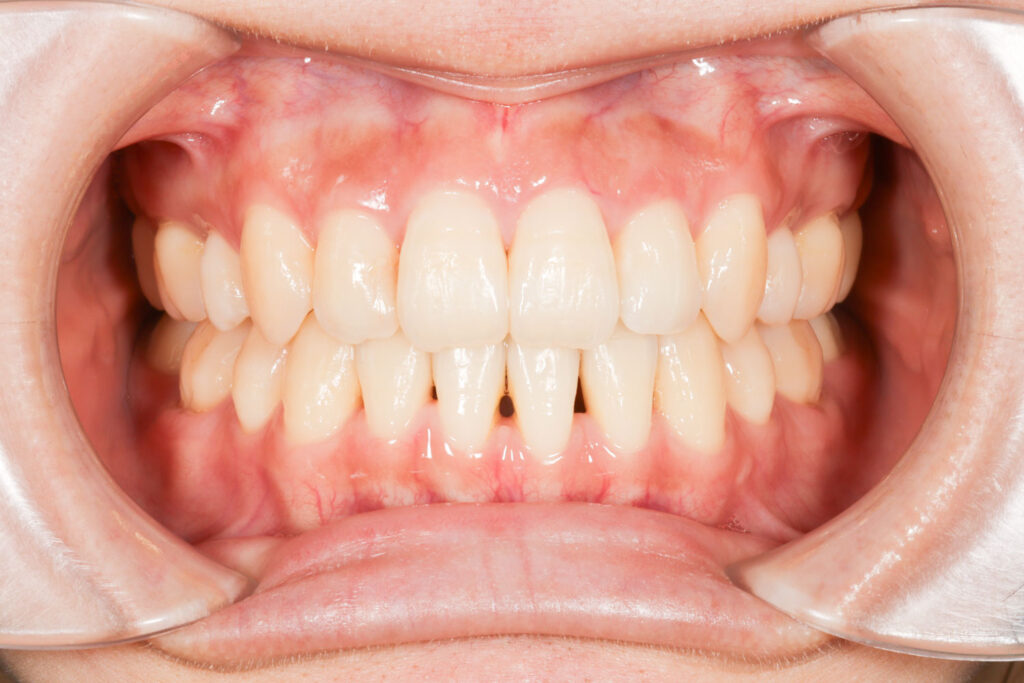

After

年齢 10代

治療装置 表側の矯正装置(ホワイトコース)

治療内容 上下左右4本抜歯

治療期間 2年1か月

リスク 歯の移動に伴う痛み、歯肉退縮、歯根吸収、歯肉炎、虫歯

主訴 ガタガタが気になる

症状 叢生(ガタガタ)

治療回数 25回程度

総額費用 105万円程度